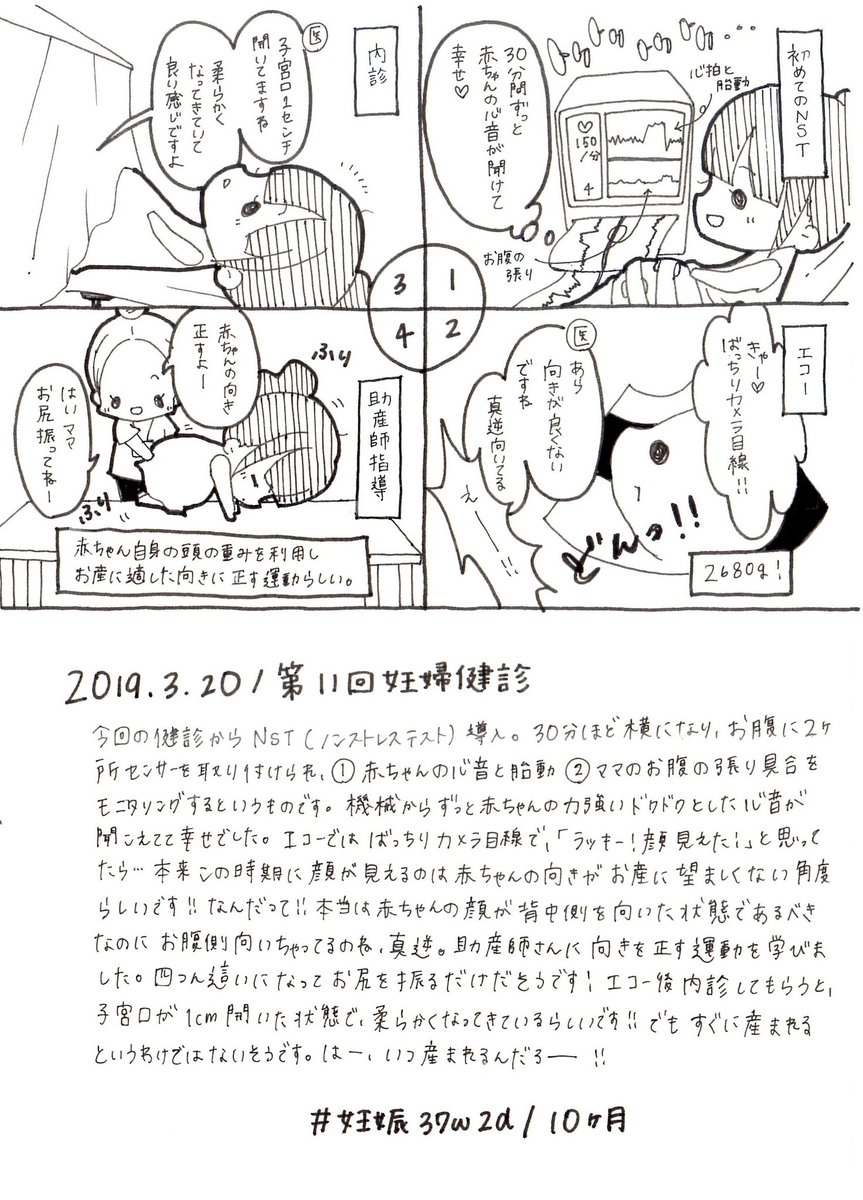

2019.3.20 もう37週に入ったのでいつ生まれてきてもいいよー! 正期産に入っての妊婦健診。逆子ではないけど赤ちゃんの表裏が真逆だそうで。それ以外は順調です! エコー・お腹の写真載せます、閲覧注意! #育児漫画 #育児日記 #妊娠 #臨月 #妊娠10ヶ月 #正期産 #妊婦健診 #ママ垢さんと繋がりたい pic.twitter.com/C5E3fv46ai

2019-09-06 11:15:42 拡大

拡大

拡大

拡大